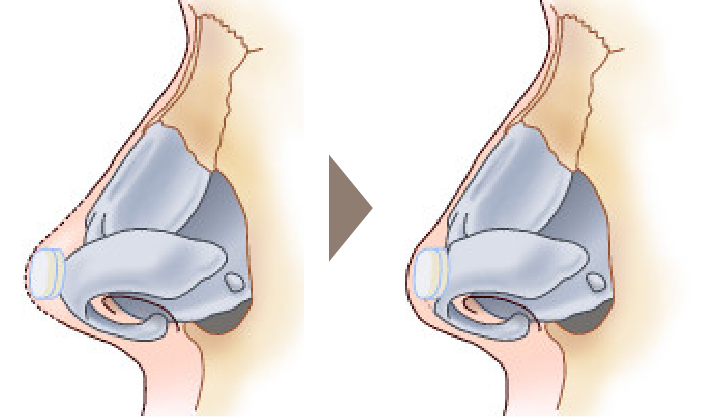

鼻中隔延長術を行った後、感染や何らかの原因で強い炎症を伴って鼻先が拘縮してしまった場合、時期を待って肋軟骨移植による修正を行う方法があります。

拘縮し鼻先や鼻尖が後退している状態の改善を図るため、open approachから拘縮をできるだけ解除します。

肋軟骨で作成したL型フレームを移植します。

肋軟骨L型フレームを外側鼻軟骨と前鼻棘に縫合固定します。

鼻翼軟骨をL型フレームに引き上げ固定します。

必要に応じて鼻柱部分に軟骨移植を追加します。

鼻先を耳介軟骨や軟部組織でカバーします。